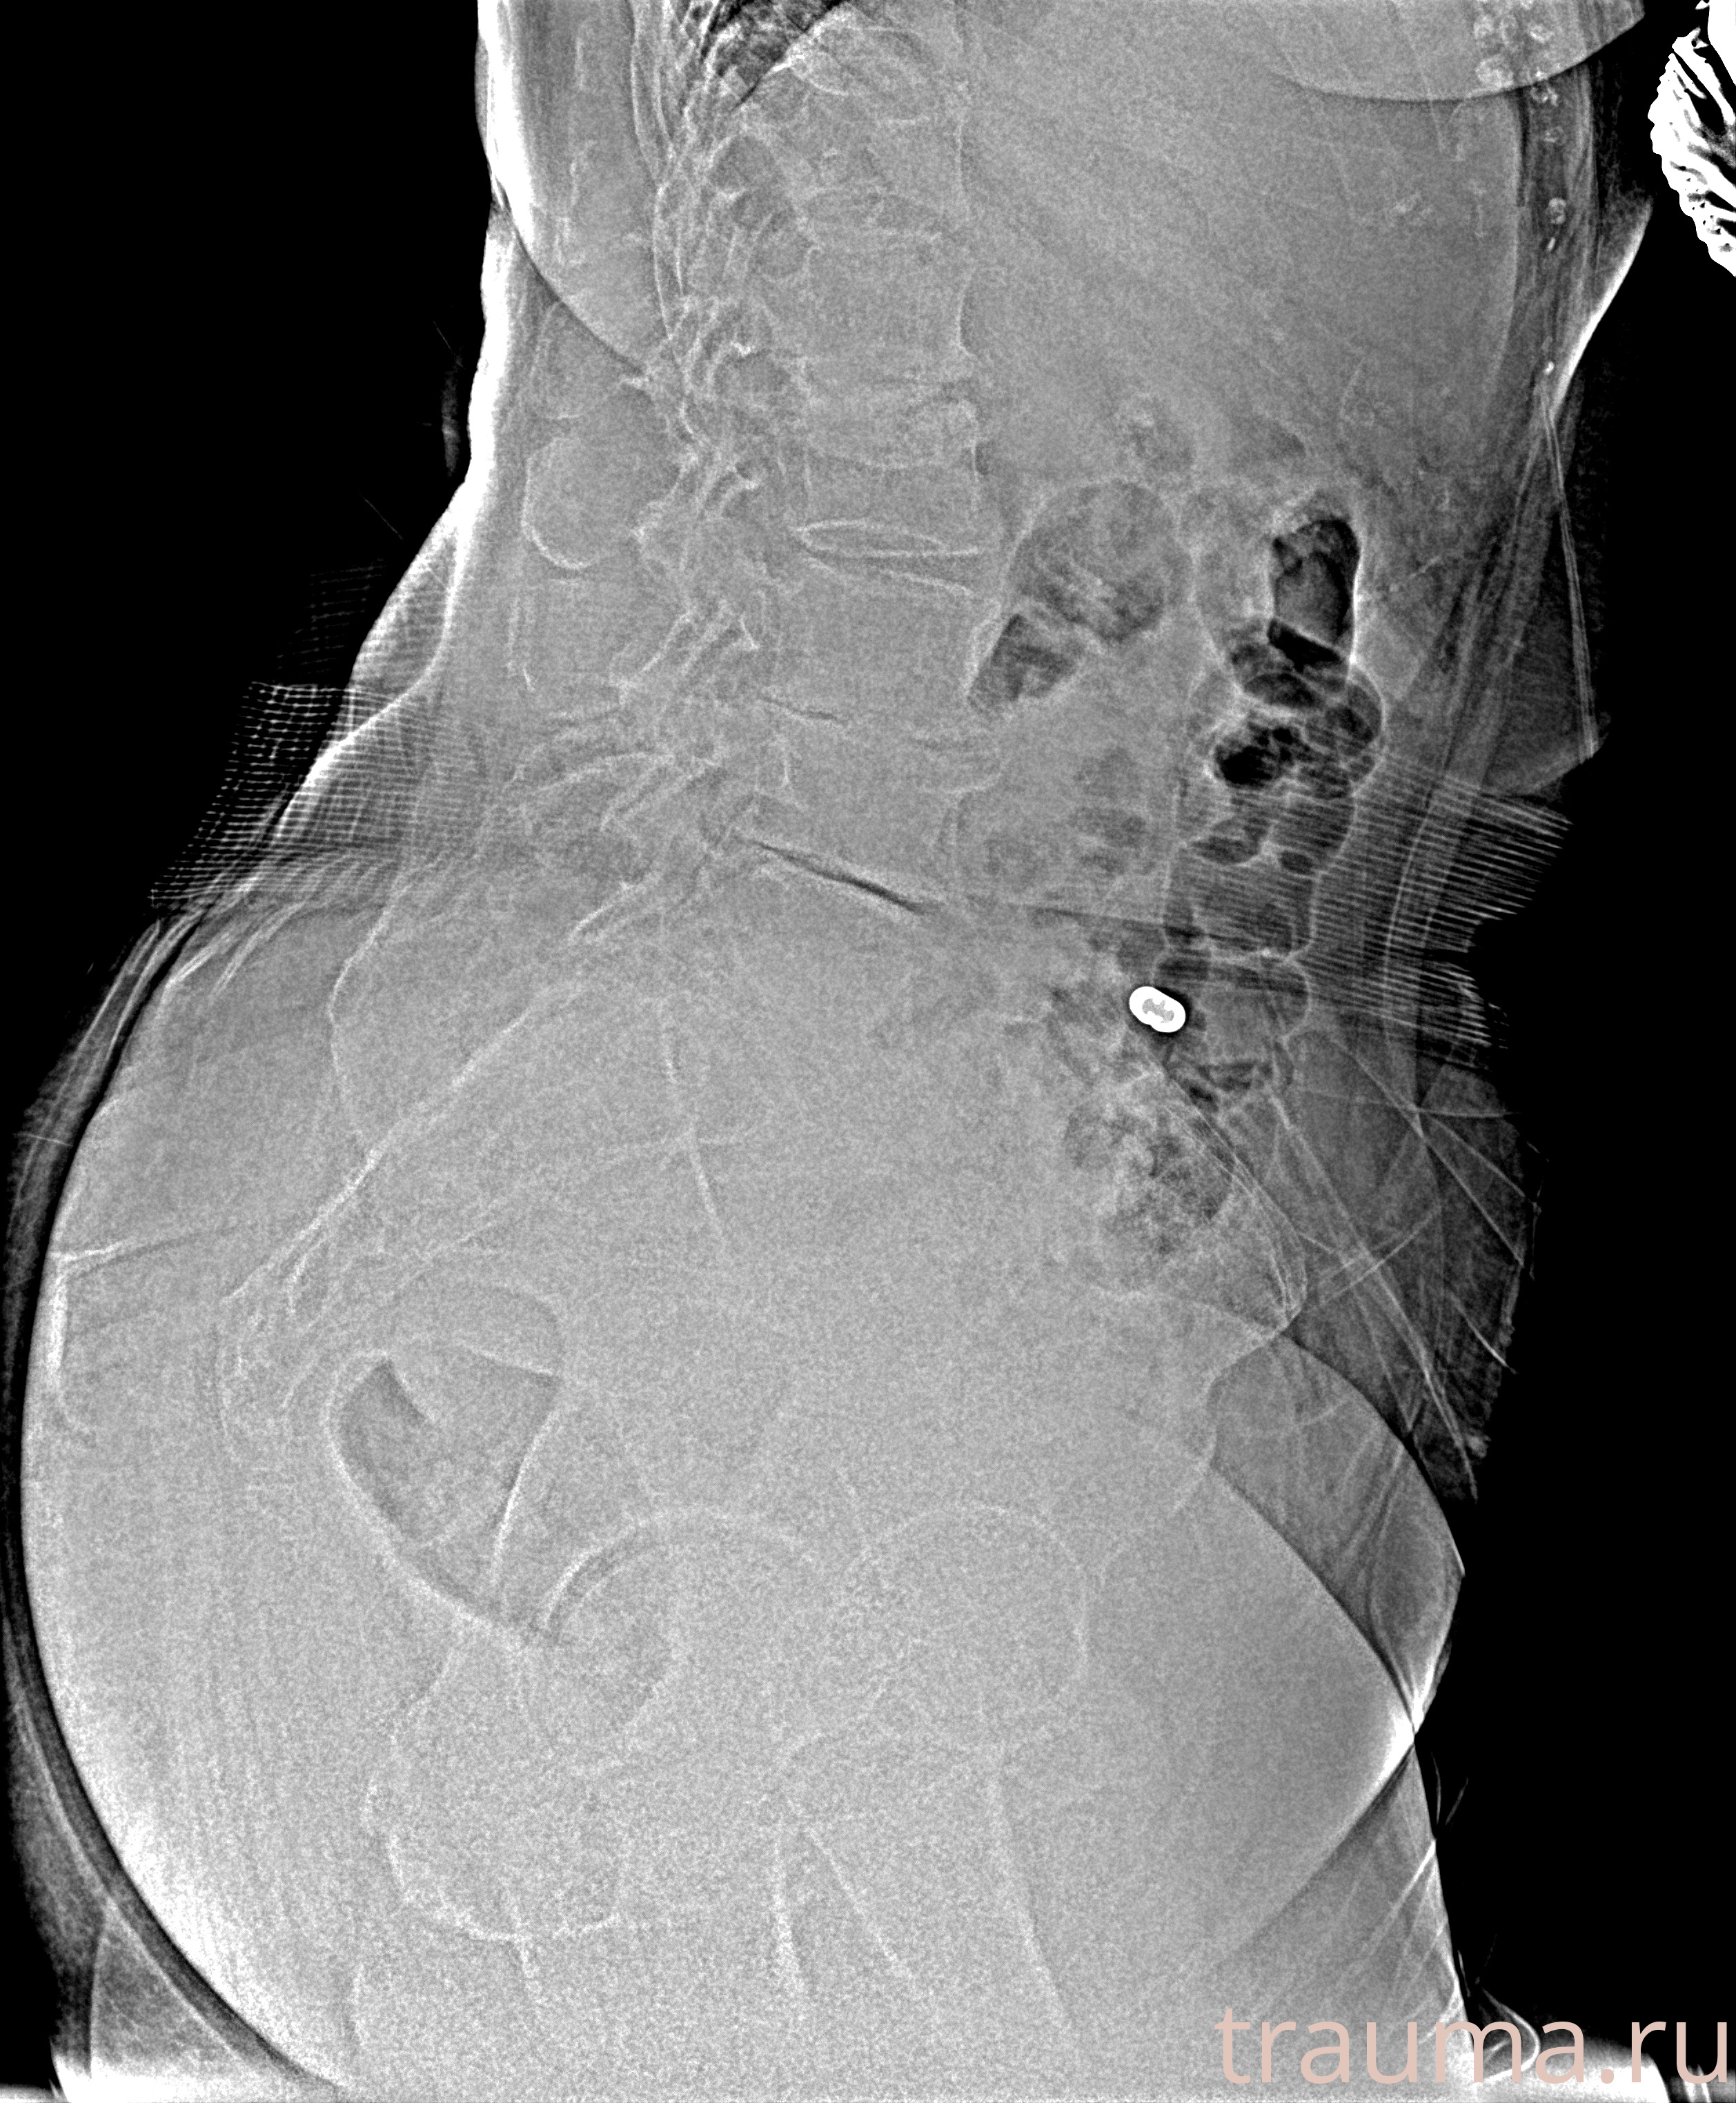

Рентген на дому: по вашему адресу приезжает врач-рентгенолог, травматолог-ортопед с мобильным рентгеновским аппаратом, проводит диагностику травмы или заболевания, делает необходимые рентгенограммы, дает рекомендации по дальнейшему лечению. Получить качественные снимки в домашних условиях возможно благодаря уникальной методике, разработанной МосРентген Центром для института  Склифосовского

при переломе шейки бедра и пневмонии от компании МосРентген Центр - партнера Института имени Склифосовского